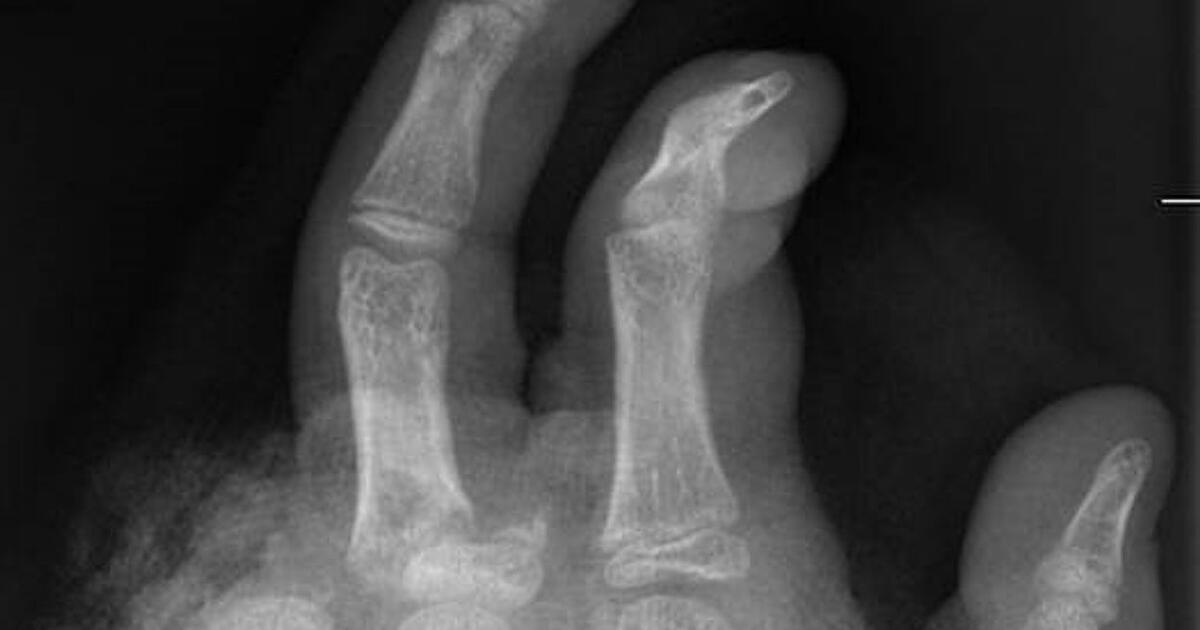

Dresden - Am Mittwoch ist Silvester. Danach sieht es vielerorts aus wie auf einem Schlachtfeld. Militärische Vergleiche sind angesichts von abgerissenen Fingern und immer wieder auch Todesfällen gar nicht...weiterlesen »

An Silvester herrscht für Handchirurgen Hochbetrieb. Viele Handverletzungen sind selbst verschuldet, erklärt eine Ärztin. Besonders häufig betroffen sei vor allem eine Personengruppe. Abgetrennte Finger,...weiterlesen »

Abgetrennte Finger, durchtrennte Sehnen, Amputationen - die Handchirurgin Leila Harhaus-Wähner hat in der Silvesternacht schon vieles gesehen. Auch in diesem Jahr rechnet die Berliner Ärztin mit zahlreichen...weiterlesen »

2024 kamen in Deutschland zu Silvester fünf Menschen bei Unfällen mit Böllern ums Leben – zwei davon in Sachsen. Ihnen wurden sogenannte Kugelbomben zum Verhängnis. „Jede Explosion geht mit Hitze und einer...weiterlesen »